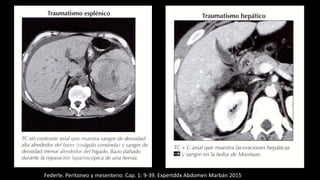

Hemoperitoneo

Federle. Peritoneo y mesenterio. Cap. 1: 9-39. Expertddx Abdomen Marbán 2015

Indicios útiles para diagnósticos

frecuentes de hemoperitoneo